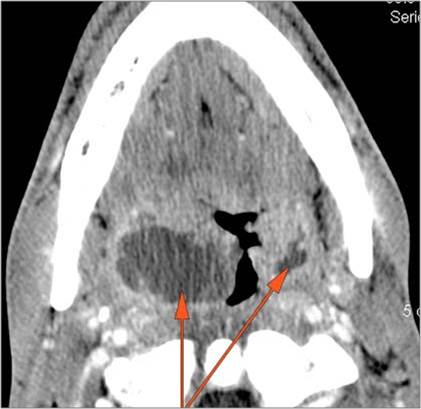

There is edema/abscess tonsillar or otherwise or likely suppurative retropharyngeal adenitis involving the oropharynx or adjacent deep tissue spaces.

There is edema/abscess within or surrounding the buccal space, masticator space, floor of the mouth, submandibular space or the adjacent superficial fascia or subcutaneous fat and skin.

If there is suppurative cervical adenopathy the purulent material outside the lymph node(s) capsule(s).